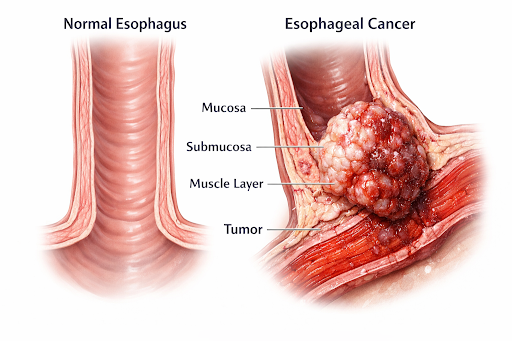

Overview of Esophageal Cancer

Esophageal cancer is a type of cancer that begins in the esophagus—the muscular tube that carries food and liquids from the throat to the stomach. It develops when the cells lining the esophagus undergo abnormal changes and begin to grow uncontrollably, gradually forming a tumor that may spread to nearby tissues or other parts of the body if not detected early.

Where It Begins

Esophageal cancer affects the lining of the esophagus and may develop in different sections—upper, middle, or lower—depending on the cancer type.

Esophageal cancer affects the lining of the esophagus and may develop in different sections—upper, middle, or lower—depending on the cancer type.

The disease typically begins when normal esophageal cells change their structure and growth behavior. These altered cells may multiply over time, forming abnormal tissue that can progress if not identified early.